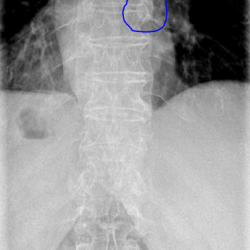

Коллеги, здравствуйте!  Женщина, 65. Первоначально снимали поясничный отдел. Глаз зацепился за кольцевидную тень за крестцом, досняли таз. Та же тень, только анфас в левой подвздошной кости...